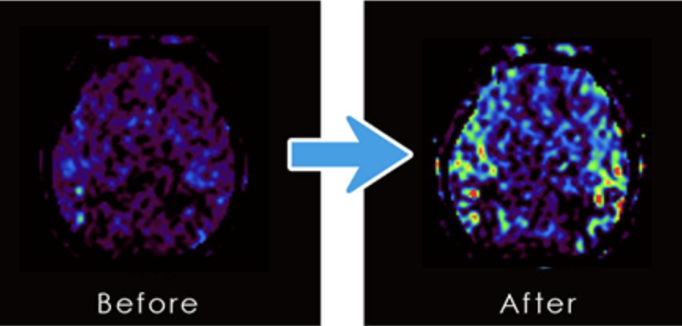

実験者6名をMRIにて脳血流を測定し、その後10分間脳大成理論のマインドテクノロジーを実践し再度MRIにて脳血流を測定しました。

その内3人の方の脳大成理論におけるマインドテクノロジー前後のCBF(脳血流)画像。

左が何もしない状態でMRI測定した写真(ビフォア)で、右が10分間マインドテクノロジーを実行してからMRI測定した写真(アフター)となります。

特に頭頂葉、頭蓋底は眼窩近傍に血流増加が見られる。

以上の結果から、脳大成理論のマインドテクノロジーを実践することにより、脳血流が向上することが明らかになりました。講座・研修での体感・体験実験(ワークス)で実感できる変化や、脳大成理論に取り組んだ後に現実に表れた変化や成果のみならず、前に示したように確実に脳に変化が現れることが実証できました。